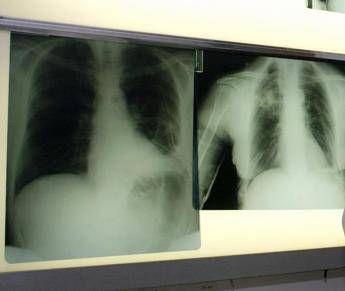

(Adnkronos) – BeOne Medicines, azienda oncologica globale, ha annunciato oggi che la Commissione europea ha approvato tislelizumab in combinazione con chemioterapia a base di etoposide e platino come trattamento di prima linea dei pazienti adulti con tumore del polmone a piccole cellule di stadio esteso (Es-Sclc). “Il tumore del polmone a piccole cellule in stadio esteso è notoriamente difficile da trattare per la sua natura aggressiva e necessita di nuove opzioni terapeutiche – afferma Silvia Novello, presidente di Women against Lung Cancer in Europe (Walce), direttore Oncologia medica all’Ospedale San Luigi Gonzaga di Orbassano e professore ordinario di Oncologia medica all’Università degli Studi di Torino – I risultati dello studio Rationale-312 mostrano che tislelizumab più chemioterapia ha migliorato la sopravvivenza rispetto al trattamento con placebo più chemioterapia, evidenziando la capacità di offrire migliori risultati per i pazienti eleggibili”.

L’approvazione nel tumore del polmone a piccole cellule di stadio esteso (Es-Sclc) – riporta una nota – si basa sui risultati di Rationale-312 (NCT04005716), uno studio multicentrico di fase 3 randomizzato, in doppio cieco, controllato con placebo, mirato a valutare l’efficacia e la sicurezza di tislelizumab in combinazione con platino (cisplatino o carboplatino a scelta dell’investigatore) più etoposide, come trattamento di prima linea dei pazienti adulti con Es-Sclc. Lo studio, che ha randomizzato 457 pazienti, ha raggiunto l’endpoint primario, mostrando un miglioramento statisticamente significativo e clinicamente rilevante della sopravvivenza globale (Os) con tislelizumab in combinazione con chemioterapia, rispetto a placebo più chemioterapia nella popolazione intent-to-treat (Itt). Come riportato sul ‘Journal of Thoracic Oncology’, all’analisi finale prevista dal protocollo la sopravvivenza mediana è risultata di 15,5 mesi per tislelizumab con chemioterapia rispetto a 13,5 mesi per placebo più chemioterapia, con una riduzione del 25% del rischio di morte. Tislelizumab più chemioterapia è stato generalmente ben tollerato e non sono stati identificati nuovi segnali di sicurezza.